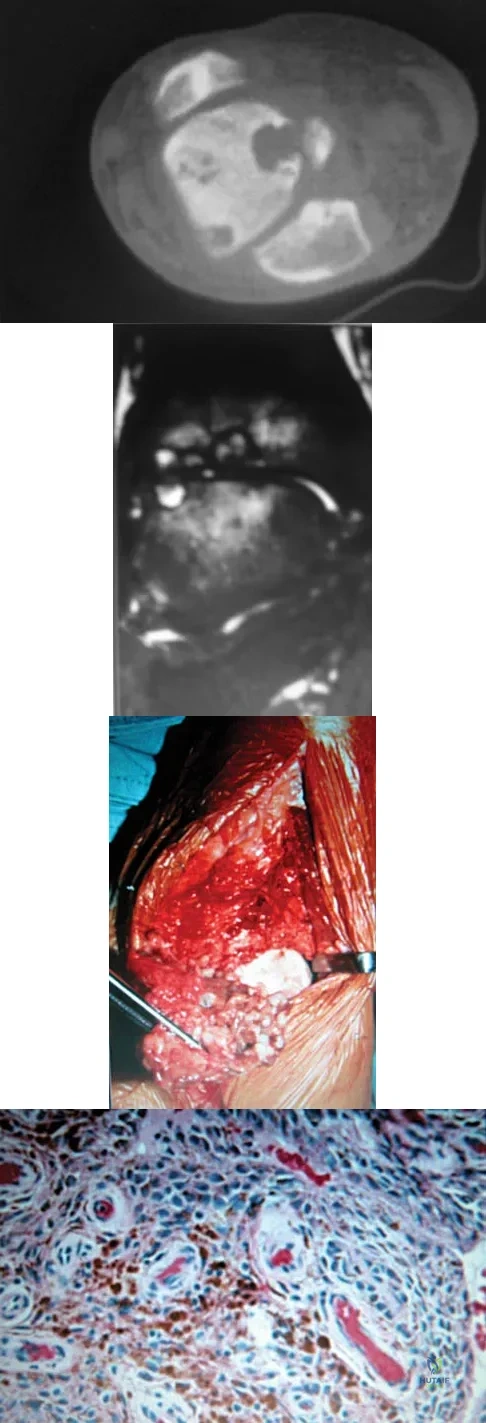

A 30-year-old man has had intermittent swelling of his right ankle for the past 6 months. He denies any history of trauma. Radiographs reveal osteolytic changes on both sides of the joint. An axial CT scan and a T2-weighted MRI scan are shown in Figures 40a and 40b. He undergoes surgical excision. An intraoperative photograph and a biopsy specimen are shown in Figures 40c and 40d. What is the most likely diagnosis?

Explanation

Pigmented villonodular synovitis often presents with intermittent swelling and minimal pain. It often occurs around joints but may be found around tendon sheaths and bursal linings. Periarticular erosions involving both sides of joints are typical, and multiple joint involvement has been described. Portions of low-signal intensity on T1- and T2-weighted images are characteristic of hemosiderin-laden processes. High-signal content is suggestive of high water content. The combination of low-signal intensity areas in intra-articular lesions with or without osseous destruction is diagnostic of pigmented villonodular synovitis. Aspiration reveals bloody or brownish fluid. The treatment of choice is synovectomy performed arthroscopically or open. Recurrence is common. Walling AK: Soft tissue and bone tumors, in Coughlin MJ, Mann RA (eds): Surgery of the Foot and Ankle, ed 7. St Louis, MO, Mosby, 1999, pp 1007-1032.